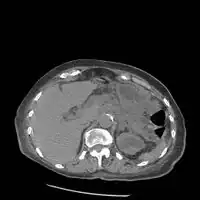

On CT scan, pancreatic and bile duct dilatation, atropy of pancreas, multiple calcifications of the pancreas, and enlargement of pancreatic glands can be found.[12]

On MRI scan, there is a low T1 signal due to inflammation, fibrosis, focal lesions, and calcifications. In those who are given with a contrast agent, there would be a higher T1 signal with late gadolinium enhancement due to compression from the fibrotic areas. The overall thickness of the pancreas will be reduced. Magnetic resonance cholangiopancreatography (MRCP) is the most useful option in accessing the pancreatic duct and bile duct.[12]